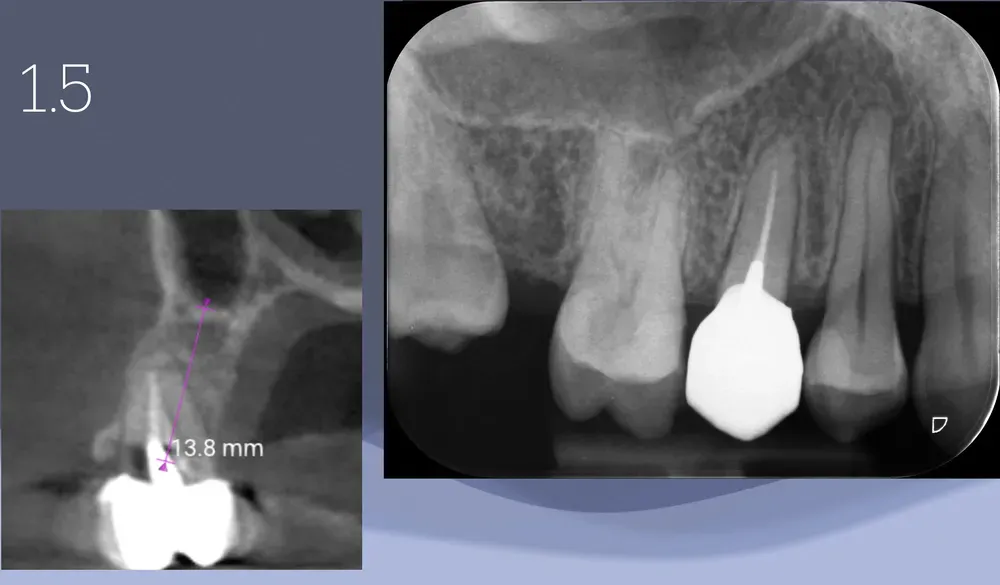

Illustrazione radiografica dell

Illustrazione radiografica dell’asse da correggere in un caso di premolare superiore con frattura radicolare.

Il Problema dell’Asse

Seguire l’alveolo esistente significa allontanare l’impianto dal centro della cresta ossea. Il risultato è prevedibile: frattura della sottile parete vestibolare durante l’inserimento, perdita del bundle bone per insufficiente spessore residuo, riassorbimento progressivo e compromissione estetica. E, in molti casi, fallimento. Il malposizionamento implantare comporta conseguenze biomeccaniche che si manifestano nel tempo.

La soluzione richiede di cambiare asse mantenendo il punto di emergenza coronale. Ma la preparazione del sito tende naturalmente a seguire il percorso di minor resistenza, che corrisponde esattamente alla direzione della radice estratta. Le frese seguono questa via. Gli strumenti rotanti cercano la zona più cedevole. È necessario forzare una direzione diversa, un asse corretto.